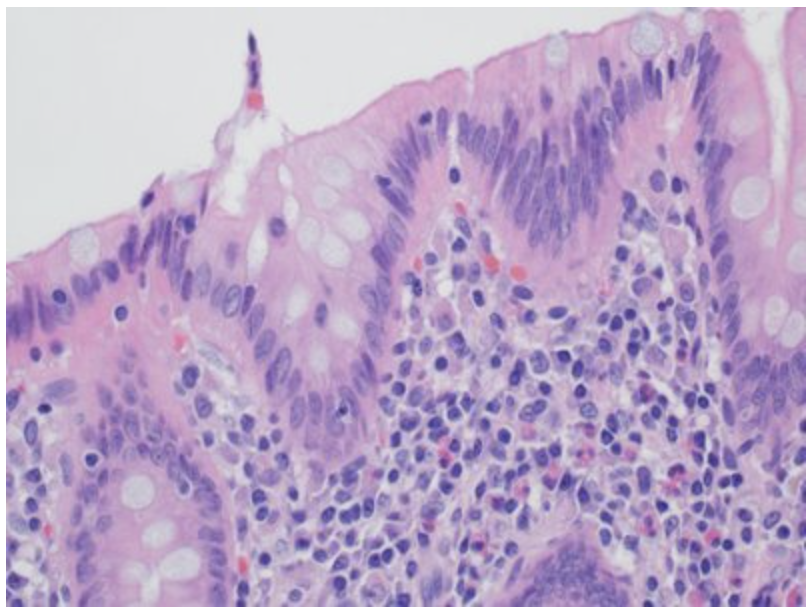

In this image, identify the component responsible for absorption and secretion!

This is a picture of a colon. The correct answer is the epithelium which lines the lumen of the colon. Remember that in the human body, the epithelial tissue’s functions include secretion, absorption and/or protection.